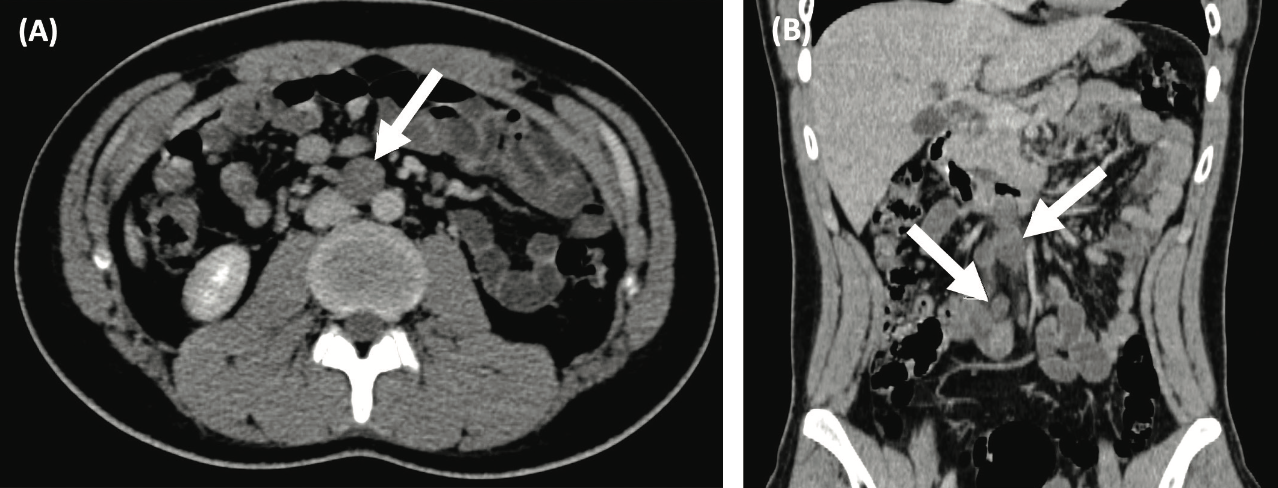

A right radical inguinal orchiectomy was performed. Pathological examination revealed a 2.4 cm by 2 cm embryonal carcinoma with tumor invasion into the tunica albuginea. Postsurgical tumor markers obtained 3 weeks after orchiectomy were β-hCG, 100.5 mUI/L (normal, <0.06 mUI/L); AFP, 1075 ng/mL (normal, 0-9 ng/mL); and LDH, 180 U/L (normal, 179 U/L). A chest, abdomen, and pelvis CT scan showed a 2.7-cm retroperitoneal lymph node enlargement, without visceral metastasis (Figure 1A and B).

Figure 1. Baseline and Follow-up Contrast Enhanced CT scans of a Nonseminomatous Germ Cell Tumor Before and After Systemic Treatment. Baseline axial (A) and coronal (B) CT scans show a 2.07-cm retroperitoneal lymph node enlargement.

Given the presence of node-positive disease with S2 serum markers, the diagnosis of a stage IIIB intermediate risk nonseminomatous germ cell tumor (NSGCT) was determined, and the patient underwent sperm banking. The patient was started on chemotherapy with 4 cycles of BEP (bleomycin, etoposide, and cisplatin), with a favorable tumor marker decline according to the Gustave-Roussy nomogram. After completion of the fourth chemotherapy cycle, serum tumor markers were negative, and 8 weeks after chemotherapy, the follow-up CT showed a 1.6-cm residual retroperitoneal lymph node conglomerate (Figure 1C and D).

(C, D) Follow-up axial and coronal CT scans after 4 cycles of bleomycin, etoposide, and cisplatin (BEP) show a partial response to systemic therapy with a residual retroperitoneal disease of 1.64 cm (arrow).